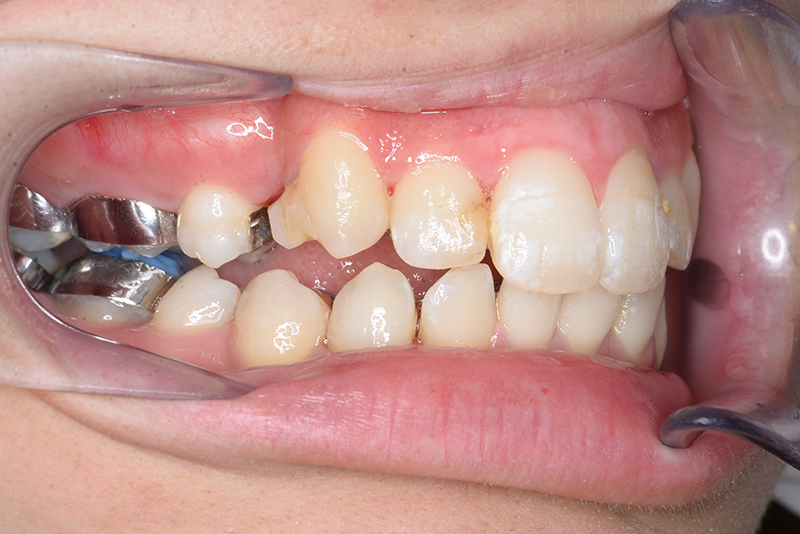

初診時

FP・IOP

口腔内所見 over jet 11.5mm、over bite 5.5mm、右側臼歯関係Full ClassⅡ級、左側end onⅡ級、上顎顎歯列はテーパー型であり、上顎中切歯は押し出されるように大きく唇側傾斜していた。下顎前歯部は叢生を呈しており、左下5は歯冠長が短く半埋伏していた。